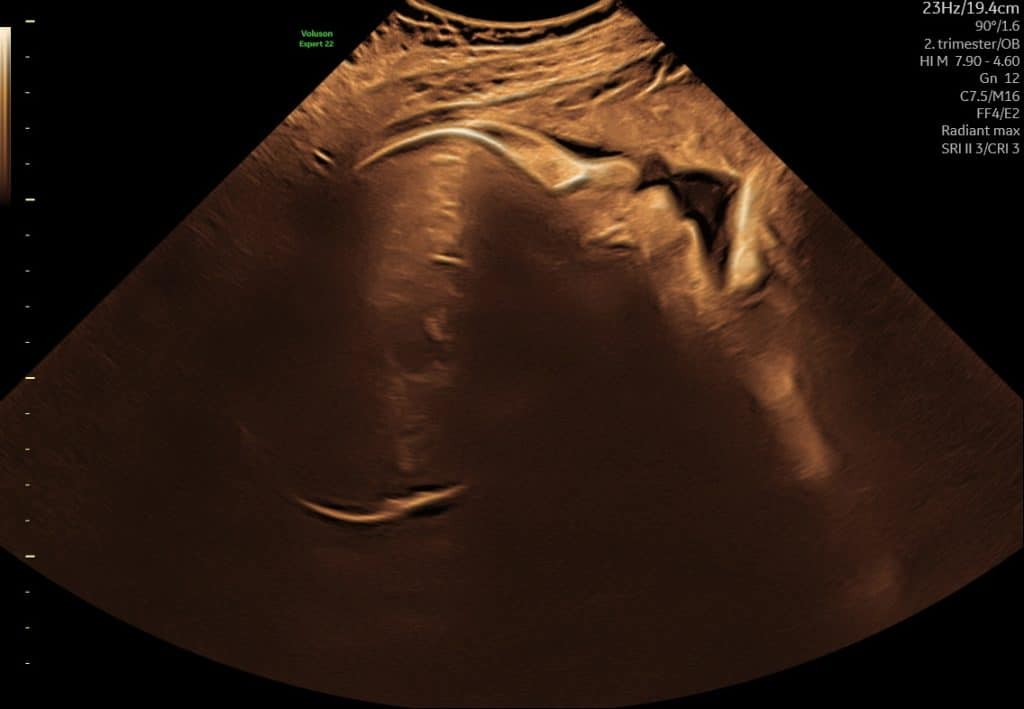

Ultralyd i uge 18–21

I denne periode udføres den store gennemgang af barnets anatomi i det offentlige. Ved ultralyd kan man typisk se:

- organer og kropsdele mere detaljeret

- rygrad, mave, blære og ekstremiteter

- barnets generelle trivsel

Fosteret fylder nu mere på skærmen, og det er ofte muligt at få meget klare billeder.

Ultralyd uge 18 ansigt i profil

Ultralyd i uge 18 som viser barnets rygsøjle set i længdesnit

Ultralyd i sen graviditet. Det er normalt, at man kun ser dele af barnet ad gangen.